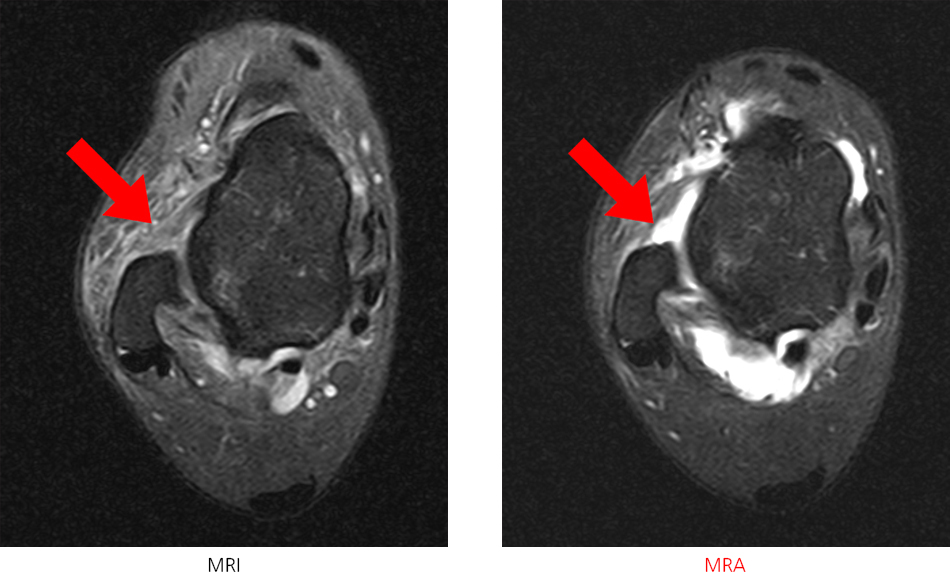

※ 발목 MRI에서는 인대 파열이 의심되는 소견을 보이고, MRA에서는 인대가 뼈에서 떨어져 있는것을 보다 정확하게 확인 할 수 있습니다.